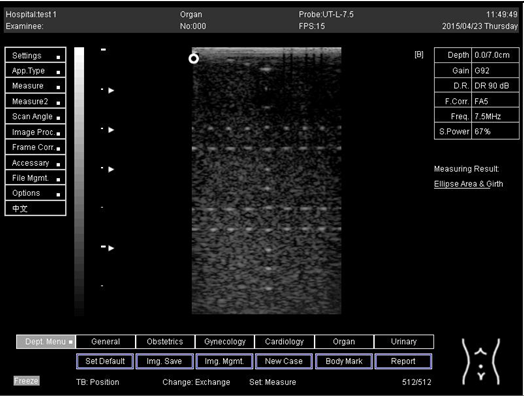

Table A6. The image taken for focal zone determination in different depth for linear probe.

Depth (cm)Diagram

5.0 The horizontal distance cannot be measured for the image of this depth

6.0 The horizontal distance cannot be measured for the image of this depth

7.0 Biomimetics 07 00130 i035

9.0 Biomimetics 07 00130 i036